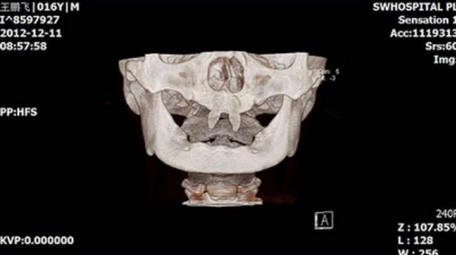

Čínský chlapec vyrostl ve dvou velmi ostrých předních zubech nutit ho, aby vypadal jako upír. V prosinci 2012 matka jménem Wang Hui vzala svého syna Wang Penfei na místní nemocnice pro vyšetření. Chongqing obecní chlapec po narození velmi špatně roste a v jeho ústech se objevily dva ostré tesák.

Wang Hui se pokusil zjistit důvod, proč se jejich syn objevil neobvyklé formace a bezpočet návštěv lékaři, ale nepřineslo to mnoho úspěchů. Lékaři z Jihozápadní nemocnice říká, že její syn může být hotový operaci pouze tehdy, když se stane dospělým.

Foto z otevřených zdrojů

Náklady na tuto operaci se mohou pohybovat od 70 000 do 80 000 RMB, to je asi 15 000 $. Podle Wang Hui se její syn stává stále více stažený a často bojuje se spolužáky, kdo o něm zašeptá, nebo se na něj podívá.